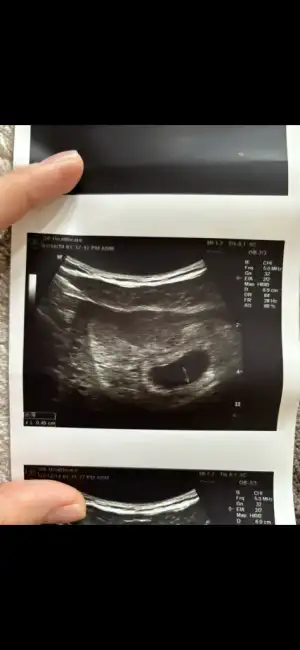

Kızlar iyi geceler hepinize. Bugün ilk kontrolüme gittim kalp atışını duyduk adet tarihim ile uyumlu çıktı. 6+2 dedi progestan verdi ağrım çok var diyince.

Mide bulantısı hiç bir şey yok bende sadece kasık ağrım çok fazla